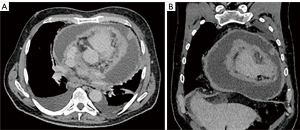

The pulmonary angiography revealed a right lobar/segmental PE (Figure 1) and a significant pericardial effusion (Figure 2) measuring 40 mm with a density of 15 HU. The patient was then admitted to the cardiology department for additional diagnostic evaluation. MSCT of the chest indicated enlarged paratracheal and subcarinal lymph nodes (Figure 3A,3B), while the MSCT of the abdomen showed no abnormalities. A transapical approach was utilized for the pericardiocentesis, during which 2.5 liters of hemorrhagic fluid were extracted and sent for cytological, microbiological, and biochemical examination. The subsequent results confirmed the type of exudative effusion, and the cytological examination indicated that there was intense and atypical growth of mesothelial cells. Thoracocentesis was subsequently performed and the analysis that followed corroborated the earlier findings. Due to suspicion of a systemic autoimmune disease or antiphospholipid syndrome, which could explain multisystem serositis (pleural and pericardial involvement), elevated inflammatory markers, thromboembolic event (PE), lymphadenopathy and constitutional symptoms, immunological tests were indicated.